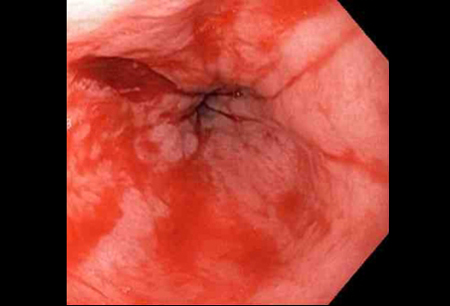

- endoscopia digestiva alta (EDA) flexível